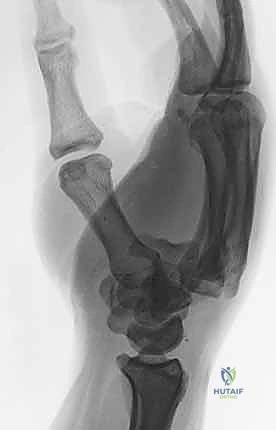

يُعتبر التشخيص الدقيق هو حجر الزاوية في نجاح العلاج. المشكلة الكبرى في كسور وخلع مفصل الكربوميتاكاربال هي أن التراكب التشريحي لعظام الرسغ والمشط في صور الأشعة السينية الأمامية الخلفية (AP View) العادية يجعل من الصعب جداً رؤية الخلع.

- صور الأشعة السينية المتخصصة (X-Rays): لا يكتفي الدكتور بالصور التقليدية، بل يطلب وضعيات تصوير خاصة (مثل الوضعية المائلة Oblique View بـ 30 درجة) التي تظهر قاعدة المشط بوضوح وتكشف الخلع الخفي.

- الأشعة المقطعية (CT Scan): في الحالات المعقدة حيث يكون الكسر مفتتاً أو الخلع متعدداً، يطلب الدكتور أشعة مقطعية ثلاثية الأبعاد (3D CT). هذه التقنية توفر خريطة دقيقة جداً لحجم الشظايا العظمية وتساعد في التخطيط الجراحي بدقة متناهية.